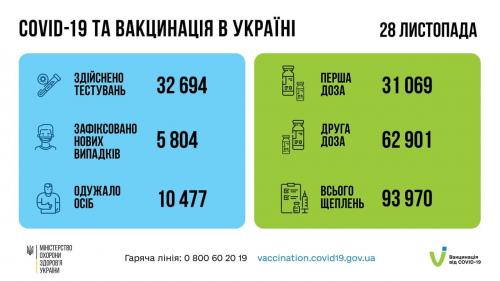

МОЗ: Уперше з початку пандемії було зроблено понад 100 тисяч ПЛР-досліджень за добу